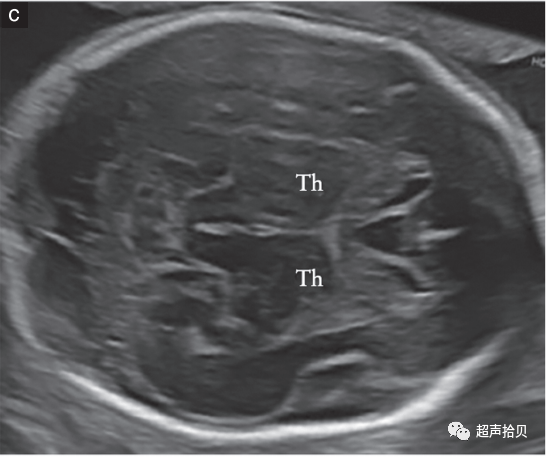

图2胎儿头部的横切面,显示标准的经脑室(a)、经小脑(b)和经丘脑(c)扫描平面。经脑室和经丘脑平面允许评估大脑半球区域的解剖完整性。经小脑平面允许评估后颅窝的小脑和大池(CM)。CP-脉络膜丛、CSP-透明隔腔、TH-丘脑。

大脑

用于胎儿大脑基本检查的标准扫描平面在更新的 ISUOG 指南20中有描述。两个横断面,通常称为经脑室平面和经丘脑平面,可以显示与大脑解剖完整性相关的大脑结构(图 2)。成像伪影掩盖了近端半球(更靠近探头的半球)。应添加第三个横断面-经小脑平面来评估后颅窝。应评估以下大脑结构:

• -侧脑室(包括脉络丛);